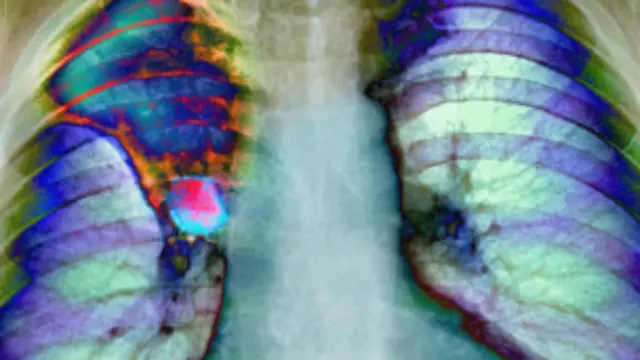

Dünya çapında en yaygın kanser türü ise genellikle sigaranın neden olduğu akciğer kanseri. 1,8 milyon vaka sayısı ile akciğer kanserinin toplam kanser hastalarındaki payı yüzde 13.